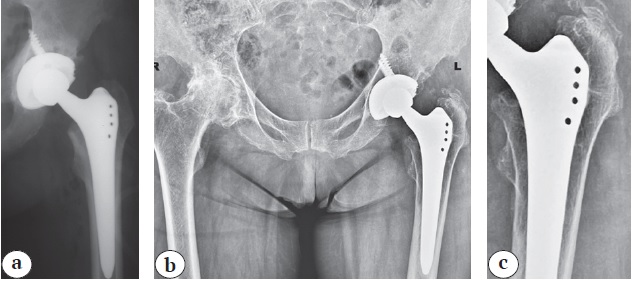

At the long-term follow-up, rather significant stress shielding (3-4 degrees) was detected in 39 cases. The third degree was detected in 27 cases out of 325 (8.3%) in patients with the Alloclassic stems (mean follow-up period 74.4 months (IQR 63.0-97.0), in patients with the SL-PLUS MIA stems — in 2 cases out of 167 (1.2%) (mean follow-up period 55.5 months). In other 10 (3.1%) observations, grade 4 stress shielding was noted when the Alloclassic stems were used (Fig. 4, 5).

Fig. 4. A 66-year-old patient in 2008 underwent left THA for primary idiopathic hip arthritis. The canal fill index in the 1st zone was 0.63, and in the 2nd and 3rd zones, it was 1.0 (a). At the time of the survey, the patient’s satisfaction was 10 points, and VAS pain score was 0. X-rays taken 13 years later show signs of stress shielding syndrome of the 4th degree, characterized by thinning of the inner and outer cortical layers to the femoral diaphysis (b).

X-rays also reveal areas of osteolysis in the proximal part of the femur, especially clear up to the level of the lesser trochanter, and osteolysis areas in the screw region in the retroacetabular zone, as well as heterotopic ossification in the area of the greater trochanter (Brooker 1-2). The enlarged X-ray visualizes bone loss (atrophy) without clear boundaries, while preserving the trabecular structure, especially at the border with the implant. The bone in this case does not exhibit focal deformations typically seen in osteolytic changes. This is because the mechanism of bone loss is related stress bypass in the distal direction, consequently resulting in reduced loading bone in the proximal regions (c)

Fig. 5. A 40-year-old patient in 2014 underwent left THA for dysplastic hip arthritis, with a canal fill index of 0.63 in the 1st zone, 0.79 in the 2nd zone, and 1.0 in the 3rd zone (a). At the time of the survey, the patient was satisfied with 10 points, and VAS pain score was 0. X-rays taken 6 years later show signs of stress shielding syndrome of the 3rd degree, characterized by thinning of the inner cortical layer below the level of the lesser trochanter (b)